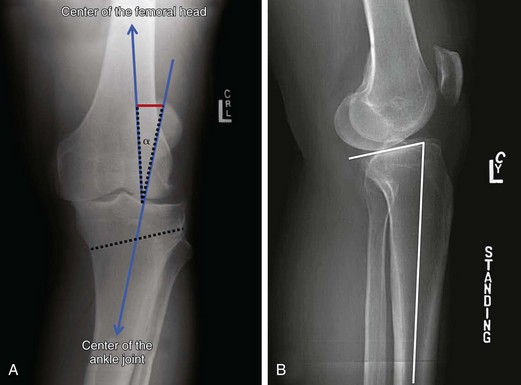

Рекурвация коленного сустава: рентгеновские снимки и объяснения